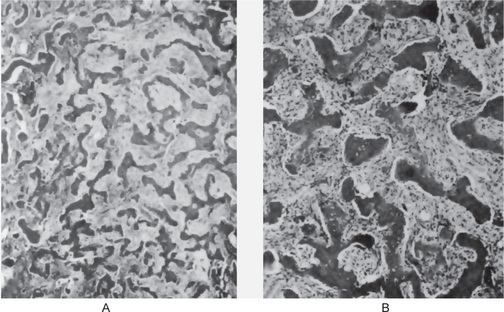

Bone biopsy is not essential for diagnosis because radiographs are usually diagnostic. Osteopetrosis is characterized by the endosteal production of bone with an apparent concomitant lack of physiologic bone resorption (Fig. 17-7). Osteoblasts are prominent, but osteoclasts are seldom found in significant numbers in tissue sections. The predominance of bone formation over resorption typically leads to the persistence of cartilaginous cores of bony trabeculae long after their replacement should have occurred in endochondral bones. The trabeculae themselves are disorderly in arrangement, and the marrow tissue present is usually fibrous.

Figure 17-7 Osteopetrosis.

A photomicrograph of a long bone showing replacement of the marrow by endosteal bone. (Courtesy of Dr Frank Vellios)

It has been reported by Johnston and his associates; however, that adult patients with benign osteopetrosis do not appear to have a deficiency in osteoclastic activity but rather an abnormality in the type and structure of bone. They found osteoblastic and osteoclastic activity with prominent remodeling of bone. However, by polarized light, the bone was found to be markedly deficient in collagen matrix fibrils and these seldom crossed from one osteon to another. This deficiency of fibrils could account for the tendency for fracture in these patients.